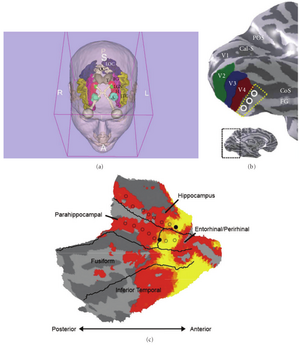

- 4.41 Molecular Drivers and Cortical Spread of Lateral Entorhinal Cortex Dysfunction in Preclinical Alzheimer’s Disease

- 4.42 Retrosigmoid Implantation of an Active Bone Conduction Stimulator in a Patient with Chronic Otitis Media